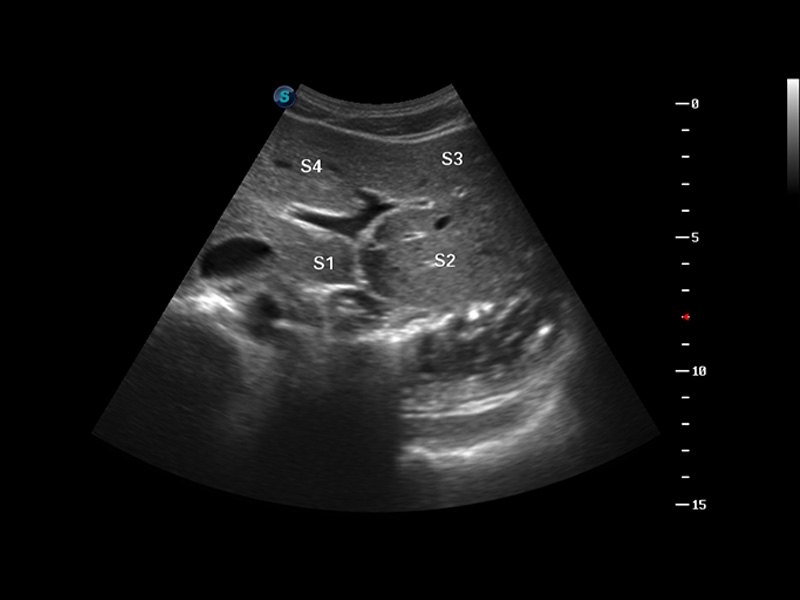

S8 EXP便携式彩色多普勒超声诊断仪是亚星官网研发的高端全身应用型便携彩超。高通道的VIS平台融合可视化(Visual)、智能化(Intelligent)和人性化(Smart)的特点,配以亚星官网自主研发生产的探头大家族,使您能够快速、准确的获得病人信息,提高工作效率的同时减轻疲劳。

成像技术

μ-Scan微米成像

谐波成像

空间复合成像

3D/4D成像